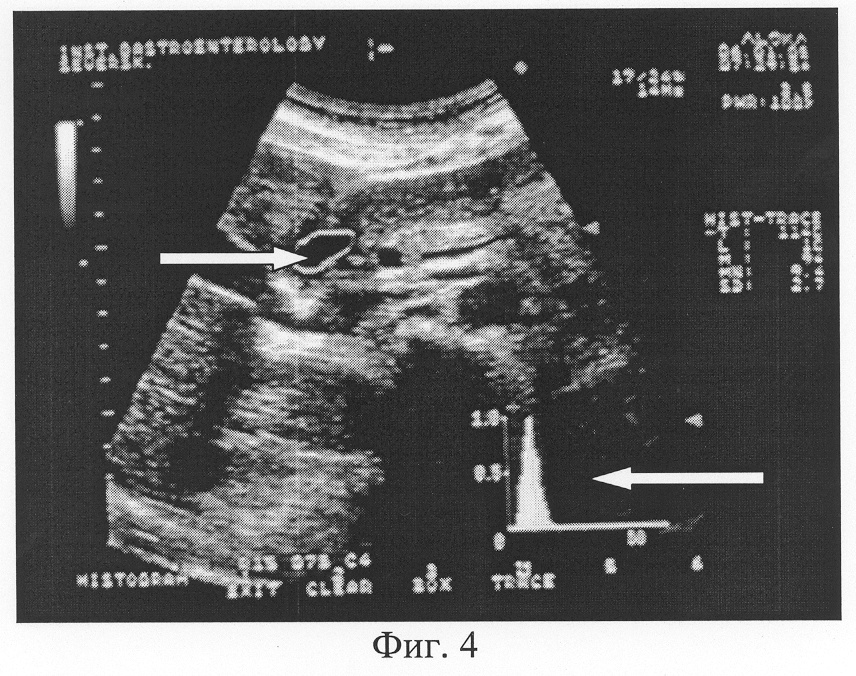

Предлагаемый способ заключается в том, что при продольном сканировании ДПК проводится гистографический анализ (величина показателя «преобладающей» эхоинтенсивности MN и графическая кривая) содержимого с использованием зоны маркера в виде двух вариантов: фиксированного квадрата с заранее заданными метрическими характеристиками (Фиг.3), либо зоны очерченной ее площади (две заложенные функции аппаратов ультразвуковой диагностики) (Фиг.4). При выполнении данного способа в зону анализа эхогенности содержимого по гистограмме следует включать наиболее характерное содержимое ДПК несколько отступя от ее стенок.

Фиг.4. Трансабдоминальное ультразвуковое исследование двенадцатиперстной кишки. Гистографический анализ содержимого ДПК с использованием зоны маркера в виде очерченной ее площади (обозначена стрелкой ). Значение показателя преобладающей эхоинтенсивности MN содержимого двенадцатиперстной кишки составило 9,4 единицы (норматив 8-12 единиц). Острый пик графической кривой гистограммы (обозначен стрелкой ) подтверждает факт однородного содержимого.